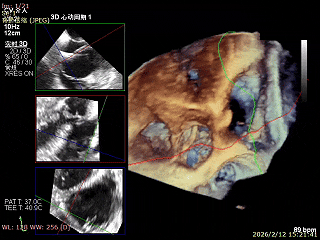

对患者三尖瓣瓣环和右冠跟瓣环距离等完成多维度评估后,充分结合其病变特点与解剖结构细节,确立以双夹K-Clip®植入为核心的精准治疗方案。手术操作中,14T型号K-Clip®植入三尖瓣后隔交界处,16T型号K-Clip®则植入前后交界处。该术式通过双点定位植入的精准操作,可有效缩减三尖瓣瓣环直径、提升瓣叶对合效能,从解剖学层面直接纠正三尖瓣反流,为患者术后顺利恢复提供关键的结构支撑。

K-Clip®手术过程

手术效果评估

反流评估:术前4+下降至1+

术前中央反流

术后中央反流

DSA双夹释放后形态无异常,锚定部位均在预期位置,RCA血流未受到影响。

术前瓣环面积

术后瓣环面积

后复查经胸心脏超声,示肺静脉、肝静脉逆流消失,二尖瓣及三尖瓣反流降低至轻度,手术效果良好。